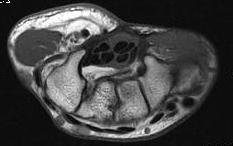

Anatomy

Transverse carpal ligament / TCL

- tuberosities of scaphoid and trapezium laterally

- pisiform and hook of hamate medially

- distal volar wrist crease proximal limit

- Kaplan's line (apex of interdigital fold between thumb and IF) distal limit

Carpal tunnel

- FCR in separate tunnel with FPL separate and below

- median nerve radial to 4 FDS

- IF / LF below MF / RF

- 4 FDP at base

- FPL separate